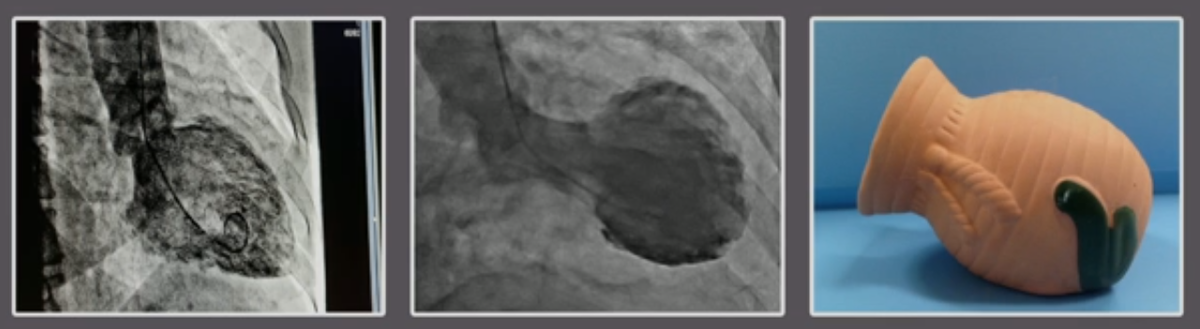

Существует заболевание сердца, впервые признанное около двух десятилетий назад, под названием «кардиомиопатия такоцубо» или «синдром разбитого сердца», при котором сердце резко ослабевает в ответ на сильный стресс или горе, например, после романтического расставания или смерти любимых.

нормальное                                    деформированное                             такоцубо

Как показывают эти картинки, скорбящее сердце посередине выглядит совсем иначе, чем обычное сердце слева. Он выглядит ошеломленным и часто раздувается в характерную форму такоцубо, изображенного справа, японского горшка с широким основанием и узкой шеей. Мы не знаем точно, почему это происходит, и синдром обычно проходит в течение нескольких недель. Однако в остром периоде это может вызвать сердечную недостаточность, угрожающие жизни аритмии и даже смерть.